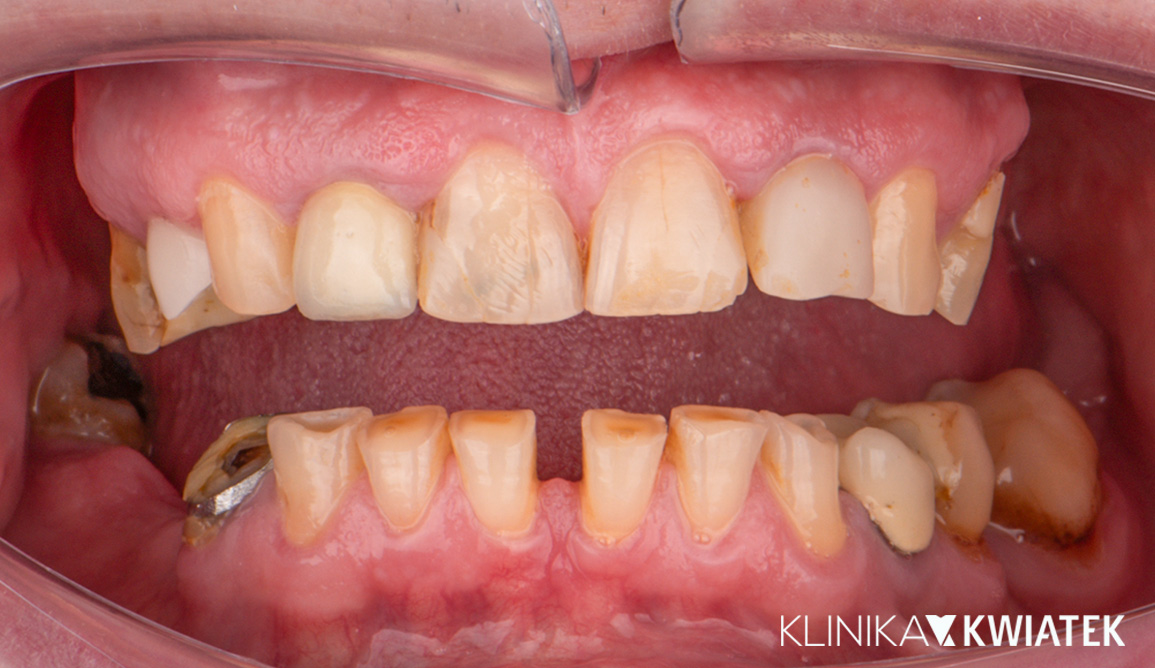

Pacjent zgłosił się z bardzo złym stanem higieny, licznymi ubytkami, zmianami okołowierzchołkowymi oraz rozległymi brakami zębowymi, które uniemożliwiały prawidłowe funkcjonowanie i estetykę uśmiechu. Rozpoczęto od sanacji jamy ustnej, leczenia zachowawczego i endodontycznego, a następnie przeprowadzono ekstrakcje, leczenie ortodontyczne, implantologiczne oraz kompleksową odbudowę protetyczną. Zakończone leczenie pozwoliło przywrócić pełną funkcję żucia, stabilny zgryz i estetyczny, harmonijny uśmiech.

PRZED

PO